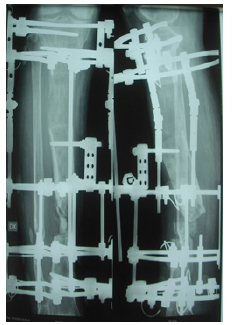

Case No 2

A male aged 60 had motor vehicle accident and sustained open fracture (Gustilo and Anderson type 3 b) of the tibia. Initially, he managed in another hospital with unplaster external fixator with screws in tibia and Kirschner wire in fibula. As there was skin loss so flap was applied over it. A few days late the flap was failed and there was pouring pus coming out of wound. In the first step he was referred to infective medicine unit of our hospital for infection control. A lot of antibiotics has been tried but insane. They have requested our unit for help in managing to eradicate infection. All antibiotics were stopped debridement with wound excision was done but it did not heal. Then all the implants were removed and daily dressing was advised to control infection but no improvement. Finally a resection of the nine centimeter of infected segment of bone done with application of Ilizarov fixator proximal osteotomy for bone transport. No antibiotics were used in this procedure. Skin loss were coverd without any procedure after application of Ilizarov that controlled the infection. With Ilizarov there is darmatotaxis which cover the skin loss. After few follow ups of bone transport the patient felt severe pain when he rotated the nuts. On examining the patient, everything was found normal except the lateral radiograph, which showed the transporting bone was deviated from its path. Deviation was corred with horizontal rods while the transport was stopped. In the next follow up visit we saw new bone formation within the gap. We stoped everything for the gap to be healed spontaneaouly without transport. In this patient, a 5 centimeter bone has been transported (Figures 7-12).

A fifty years old smoker had a history of motor vehicle accident and fracture of femur that was fixed with plate and screws. The plate was broken and was removed and intramedullary nail was put in with iliac crest bone graft. It became infected and was removed. Then uniplanar external fixator was applied but neither infection control nor union achieved. After three years of the initial trauma the patient again present to us for the same problem. Initially we stopped all medicines and stressed the patient for cession of smoking. After three months of cession of smoking, We applied Ilizarov fixator did proximal corticotomy for transport and removed the dead ends till bleeding ends which created a gap of 6 centimeter. After one month of transport there was sever pain while rotating the nuts. When we did radiographs, we saw callus formation in front of transport segment. we stopped the transport and advise the patient for active exercises and regular follow up at one month interval after six month the gap was filled and bone healed without any intervention.